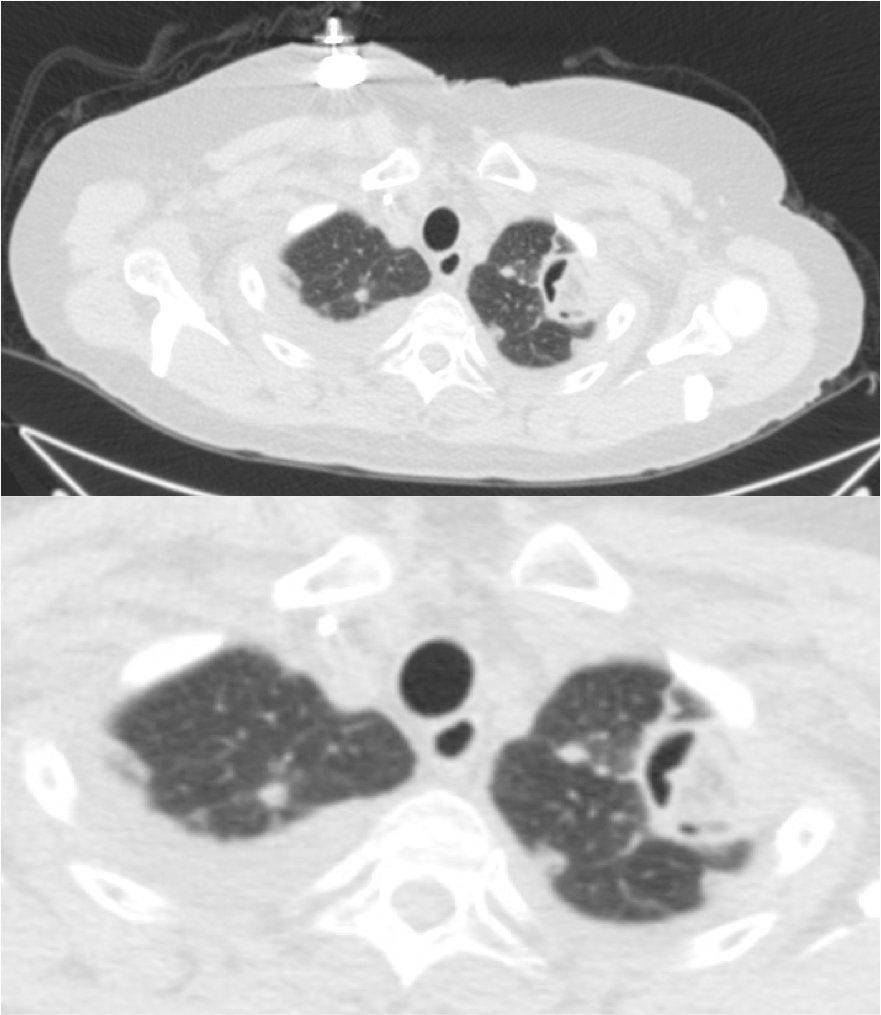

Invasión de arterias de pequeño y mediano calibre por el aspergillus que formaran nódulos de necrosis o infartos hemorrágicos. Se da en pacientes inmunocoprometidos (SIDA), tasplantados, bajo tratamiento con quimioterapia, de difícil tratamiento como la leucemia resistente, linfoma, mieloma o bajo tratamiento con corticoides (enf, autoimunes) que padecen una neutropenia funcional.

Clinica: Fiebre + tos + disnea (ALTA mortalidad). Galactomanano +.

Hallazgos radiológicos: TAC, nódulos que pueden estar rodeados de halo de vidrio deslustrado (signo del halo). Estos hallazgos corresponden a infartos hemorrágicos (Diagnóstico diferencial: mucor, cándida, CMV, Hepres simple, Wegener, sarcoma de Kaposi, metástasis hemorrágicas. También puede haber «Signo de aire creciente» por necrosis de fragmentos hemorrágicos que se desprenden del parénquima sobre todo en el periodo de convalescencia.